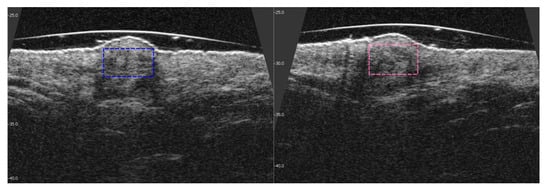

3.3. Visible and Ultrasound Changes in Scar Area